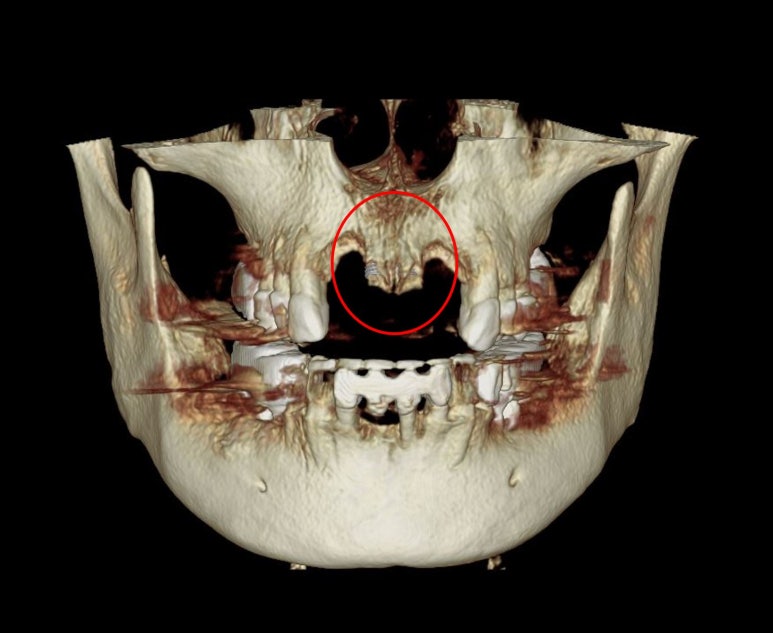

보시다시피 앞니 네개가 제거는 되었지만, 정작 뼈는 가운데 부분만 말안장처럼 남아있어요.

가운데 남은 요 부위에 두개의 임플란트를 심어보기로 계획했어요.

그리고 양 옆에 비어있는 부분은 뼈이식을 무지하게 많이 해보기로 했습니다.

뼈이식을 꼭 해야합니다. 왜냐?

안하게되면, 그 부분만 푹 꺼진채로 낫게되고 이상적인 치아의 형태를 만들어주기 어렵기 때문이죠.

axial view를 보시면, #12,22 부위에 정말로 엄청난 골소실이 있음을 보실 수 있을겁니다.